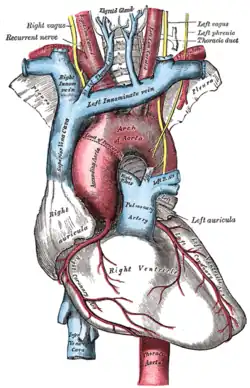

- O nervo frênico direito passa sobre a artéria braquiocefálica, posterior à veia subclávia e então atravessa a raiz do pulmão direito anteriormente, em seguida deixando o tórax, passando através da abertura do hiato da veia cava no diafragma no nível de T8. O nervo frênico direito passa sobre o átrio direito.

- O nervo frênico esquerdo passa sobre o pericárdio do ventrículo esquerdo e perfura o diafragma separadamente.

O arco da aorta e seus ramos.

O arco da aorta e seus ramos. -